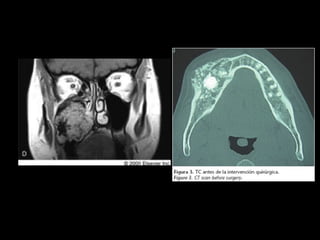

2. CT scan in case of larger lesions and esp maxillary

ameloblastoma

4. Maxillary resections often end in maxillectomy with wide

margin clearance from the sinus, nasal and infratemporal

regions